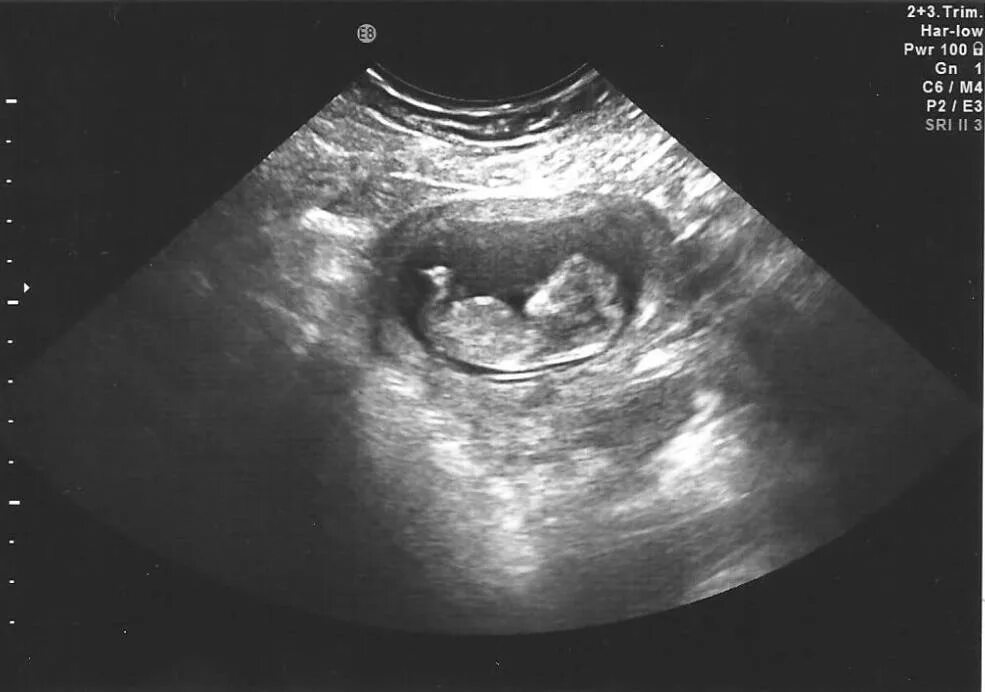

9 5 неделя беременности